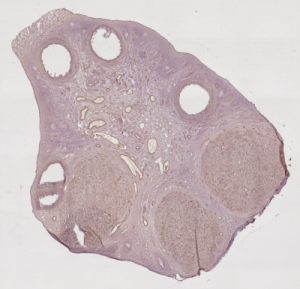

Imaging study of the ovarian function

This work takes place in the Cooperative Research Initiative named REGulation of Ovulation (REGLO). This CRI aims to study the follicular development in mammals, and proposes mathematical models that allow to follow the granulosa cell population, and then to predict the outcome of the follicular development (ovulation or degeneration) with respect to the hormonal environment. To provide the developed models with quantitative data, this work aims at reconstructing a 3-D image of the ewe’s ovary from a series of 2-D stained histologic images.

Elaboration of this atlas consists in co-registering the histological and {\em post mortem} MR data of the same subject. First, realignment of the histological sections into a reliable three dimensional volume is performed. Then the reconstructed volume is registered with the post mortem MR image. To insure three dimensional integrity of the histological reconstructed volume, a reference volume is first constructed from photographs of the unstained surface of the frozen brain. This reference is then used as an intermediate volume for, on the one hand, independant alignment of each histological section with its corresponding optical section and on the other hand, three dimensional registration with the post mortem MR image.